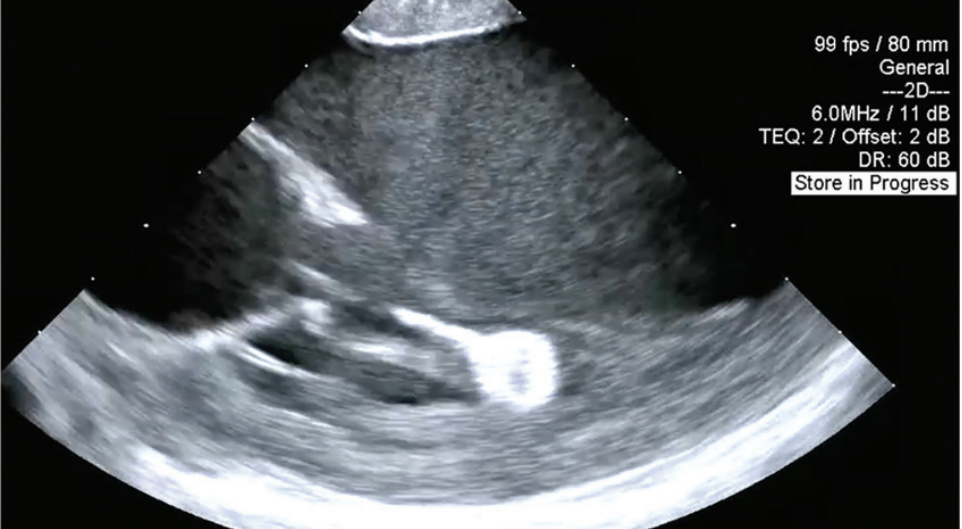

A 54-year-old man with coronary artery disease status post stenting of the right coronary artery and systemic sclerosis with subendocardial fibrosis of the mid and basal inferoseptum and inferior wall on cardiac magnetic resonance imaging was referred for frequent, highly symptomatic, unifocal, premature ventricular contractions (PVCs) with a right bundle superior axis morphology. He was in ventricular bigeminy when seen in clinic (Figure 1) and had a PVC burden of 27% on a recent Holter. He underwent an attempted ablation procedure a few months earlier, during which the PVCs were mapped to the posterior papillary muscle and inferior left ventricular (LV) base. Activation times were reported to range from 0 to -20 milliseconds pre-QS; however, ablation was unsuccessful. What factors contributed to the unsuccessful ablation, and what considerations should be made for the redo procedure?

The patient underwent a repeat procedure using a 9-mm lattice-tip, dual-energy RF/PF ablation catheter (Affera Mapping System, Medtronic) with a transseptal approach guided by intracardiac echocardiography. This approach enabled ultra-high-density mapping of the heads of the posterior papillary muscle and surrounding area (Figure 2 and video). At a site near the mitral annulus at approximately the 6:30 position, where an atrial electrogram was recorded during sinus rhythm, ventricular activation of the PVC occurred approximately 15 milliseconds pre-QRS. A single RF lesion eliminated the PVCs. A second RF lesion and a single PFA lesion were delivered. There was no recurrence of PVCs during the overnight period.